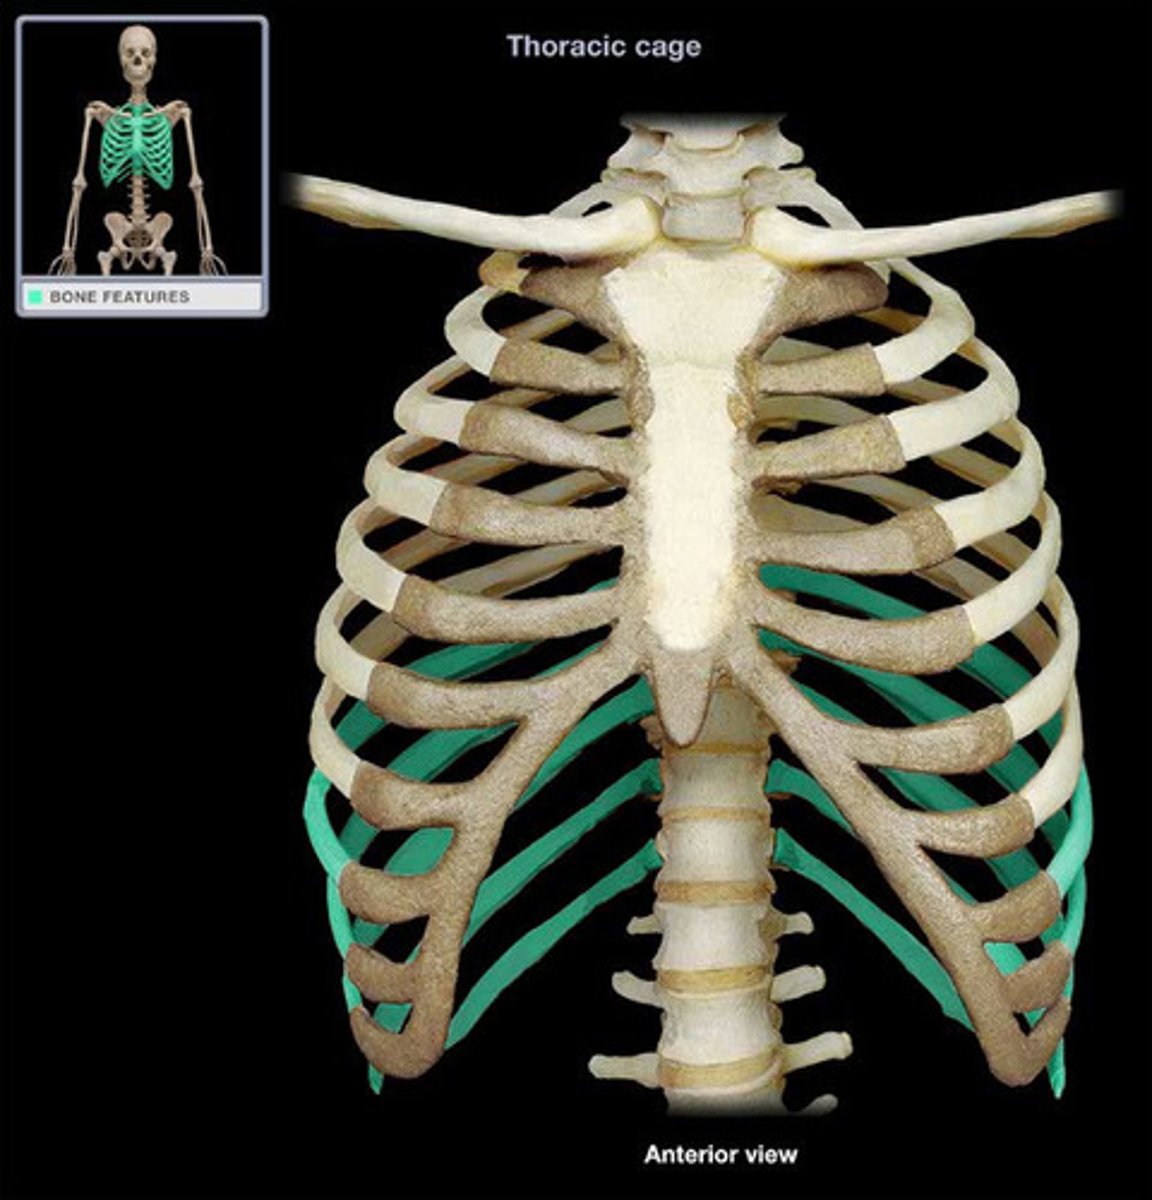

False Ribs

Sternum

Manubrium

Body

Xiphoid Process